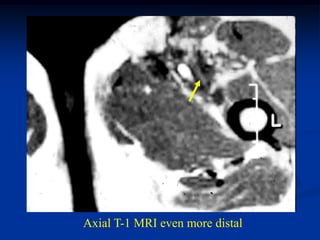

Case #304

Axial T-1 MRI

21 year female with lymphangioma inguinal area

Axial T-1 MRI more distal

Axial T-1 MRI even more distal